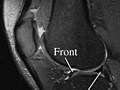

• Hay desgarros de ligamentos o meniscos.

• Hay desgarros de tendones. La resonancia magnética también puede mostrar un engrosamiento, lo que indica una cirugía o un desgarro que tuvo en el pasado o sobrecarga repetida.